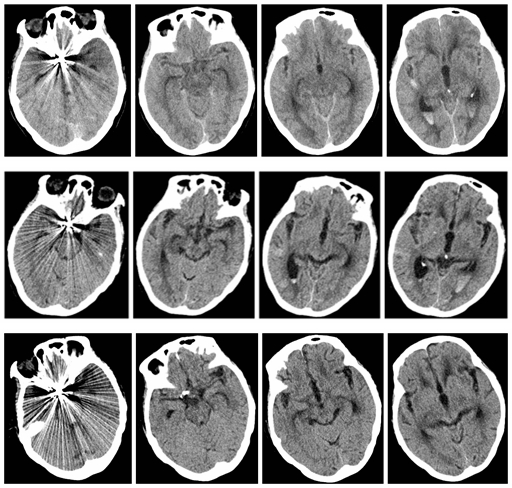

术后第一天、术后一周、术后一个月CT对比图 基于本地区发病率明显高于其他地区,所造成的经济负担甚至社会负担也较为突出,因病致贫返贫的家庭众多。院长黄纯海高度重视,要求医院教学培养工作要面向基层和乡村亟需解决的医疗卫生困点、难点,助力健康扶贫成果与乡村振兴有效衔接,培养更多基层百姓健康的“守门人”。案例成型前期,院长黄纯海多次指导修改,最终形成优秀教学案例搬进课堂。

术后第一天、术后一周、术后一个月CT对比图